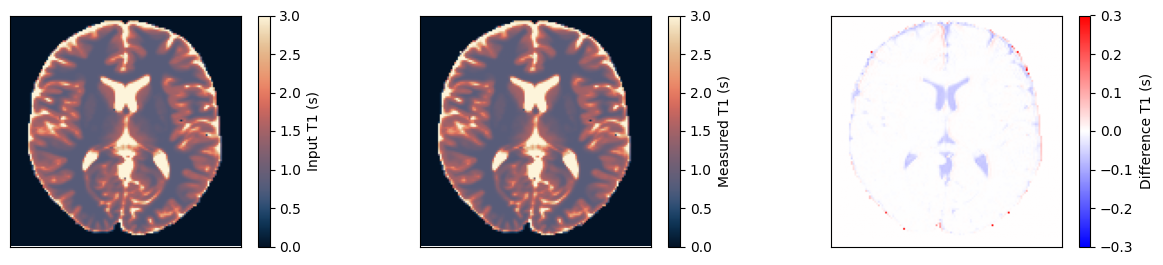

Estimate the T1 maps#

We use a dictionary matching approach to estimate the T1 maps. Afterward, we compare them to the input and ensure they match.

fig, ax = plt.subplots(1, 3, figsize=(15, 3))

for cax in ax:

cax.set_xticks([])

cax.set_yticks([])

im = ax[0].imshow(t1_input, vmin=0, vmax=3, cmap=Colormap('lipari').to_mpl())

fig.colorbar(im, ax=ax[0], label='Input T1 (s)')

im = ax[1].imshow(t1_measured, vmin=0, vmax=3, cmap=Colormap('lipari').to_mpl())

fig.colorbar(im, ax=ax[1], label='Measured T1 (s)')

im = ax[2].imshow(t1_measured - t1_input, vmin=-0.3, vmax=0.3, cmap='bwr')

fig.colorbar(im, ax=ax[2], label='Difference T1 (s)')

relative_error = np.sum(np.abs(t1_input - t1_measured)) / np.sum(np.abs(t1_input))

print(f'Relative error {relative_error}')

assert relative_error < 0.01

Relative error 0.004944732412695885